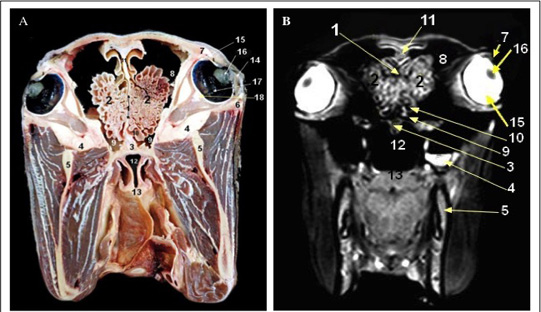

Cross sectional anatomy (Panel A) and MR image (Panel B) of horse head at the level of the molar teeth. 1) Upper molar teeth; 2) Lower molar teeth; 3) Vomer; 4) Maxilla bone; 5) Dorsal conchal bulla; 6) Ventral conchal sinus; 7) Rostral maxillary sinus; 8) Masseter muscle; 9) Pteyrgoid muscle (medial part); 10) Palatoglossal fold.

Cross sectional anatomy (Panel A) and MR image (Panel B) of horse head at the level of the diastema. 1) Ramus of mandible; 2) Nasal bone; 3) Concho frontal sinus (rostral part); 4) Fronto-maxillary opening; 5) Caudal maxillary sinus; 6) Dorsal nasal sinus (Caudal end of dorsal nasal concha); 7) Nasopharynx; 8) Soft palate; 9) Masseter muscle; 10) Pteyrgoid muscle (medial part).

Cross sectional anatomy (Panel A) and MR image (Panel B) of horse head at the level of the perpendicular plate of ethmoidal bone.1) Perpendicular plate of ethmoidal bone; 2) Ethmoid labyrinth (ethmoid conchae); 3) Vomer bone; 4) Maxilla; 5) Mandible; 6) Zygomatic arch; 7) Orbit; 8) Conchofrontal sinus (caudal part); 9) Sphenopalatine sinus; 10) Middle conchal sinus; 11) Septum of frontal sinus; 12) Nasopharynx; 13) Soft palate; 14) cornea; 15) Sclera; 16) Lens; 17) Retina; 18) Extra-ocular muscles.